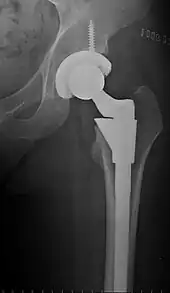

Post-operative projectional radiography is routinely performed to ensure proper configuration of hip prostheses.

The direction of the acetabular cup influences the range of motion of the leg, and also affects the risk of dislocation.[9] For this purpose, the acetabular inclination and the acetabular anteversion are measurements of cup angulation in the coronal plane and the sagittal plane, respectively.

Center of rotation: The horizontal center of rotation is calculated as the distance between the acetabular teardrop and the center of the head (or caput) of the prosthesis and/or the native femoral head on the contralateral side.[80] The vertical center of rotation instead uses the transischial line for reference.[80] The parameter should be equal on both sides.[80]